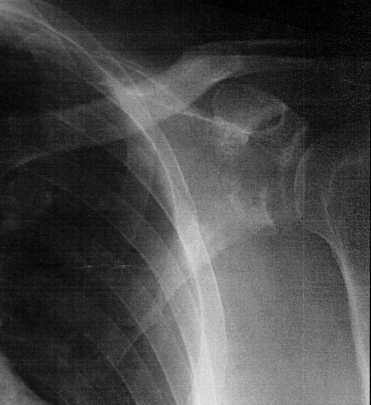

The PA returned. “You have a fractured shoulder. An orthopedic surgeon is on the way to see you,”he said.

Great. I was shocked. Stupidly I thought that once the arm popped back in the socket that I would be fine. Hah! Life is never simple.

Anyway the surgeon sees the result of the scan. “Guess what?” he tells me. “A piece of the socket broke off when you dislocated your humerus (upper arm bone).” He gave me a sling and brace and had me promise to keep my shoulder and left arm immobile and to come see him in a week.